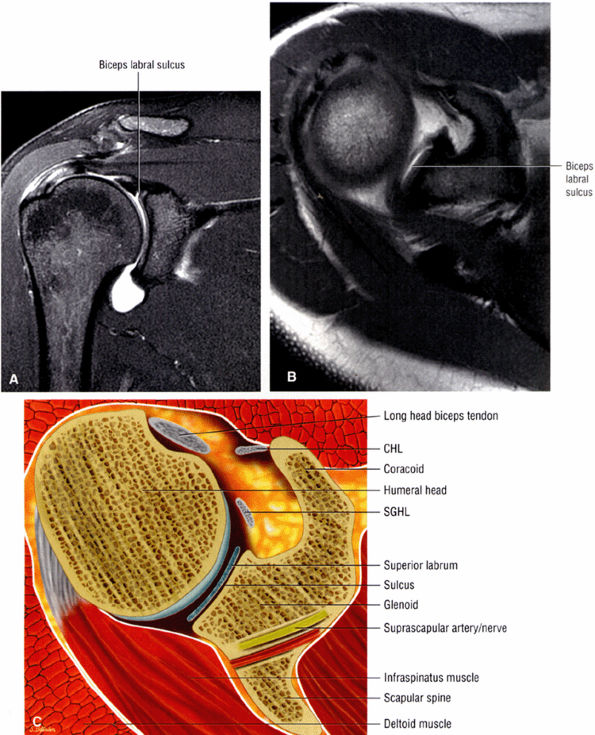

FIGURE 8.78 ● Type 2 BLC with normal superior sulcus on coronal FS PD (A) and axial PD (B) images with intra-articular contrast. (C) Corresponding axial color cross-section demonstrating the sulcus of a type 2 BLC. This sulcus should not be mistaken for detachment of the superior labrum.